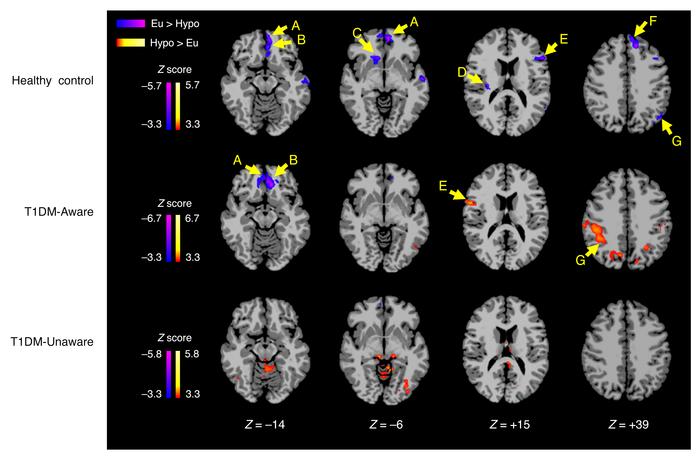

Figure 5

Differences in regional brain responses between mild hypoglycemia and euglycemia conditions.

Axial slices of healthy control (n = 13), T1DM-Aware (n = 16), and T1DM-Unaware (n = 13) subjects showing differences in brain responses to mild hypoglycemia (Hypo-Eu) (covaried by age and BMI, threshold of P < 0.001, 2-tailed, FWE whole-brain corrected). Regions identified as: A = ventromedial prefrontal cortex (vmPFC); B = orbitofrontal cortex (OFC); C = right ventral striatum/caudate; D = right insula; E = ventrolateral prefrontal cortex (vlPFC); F = dorsolateral prefrontal cortex (dlPFC); G = angular gyrus.